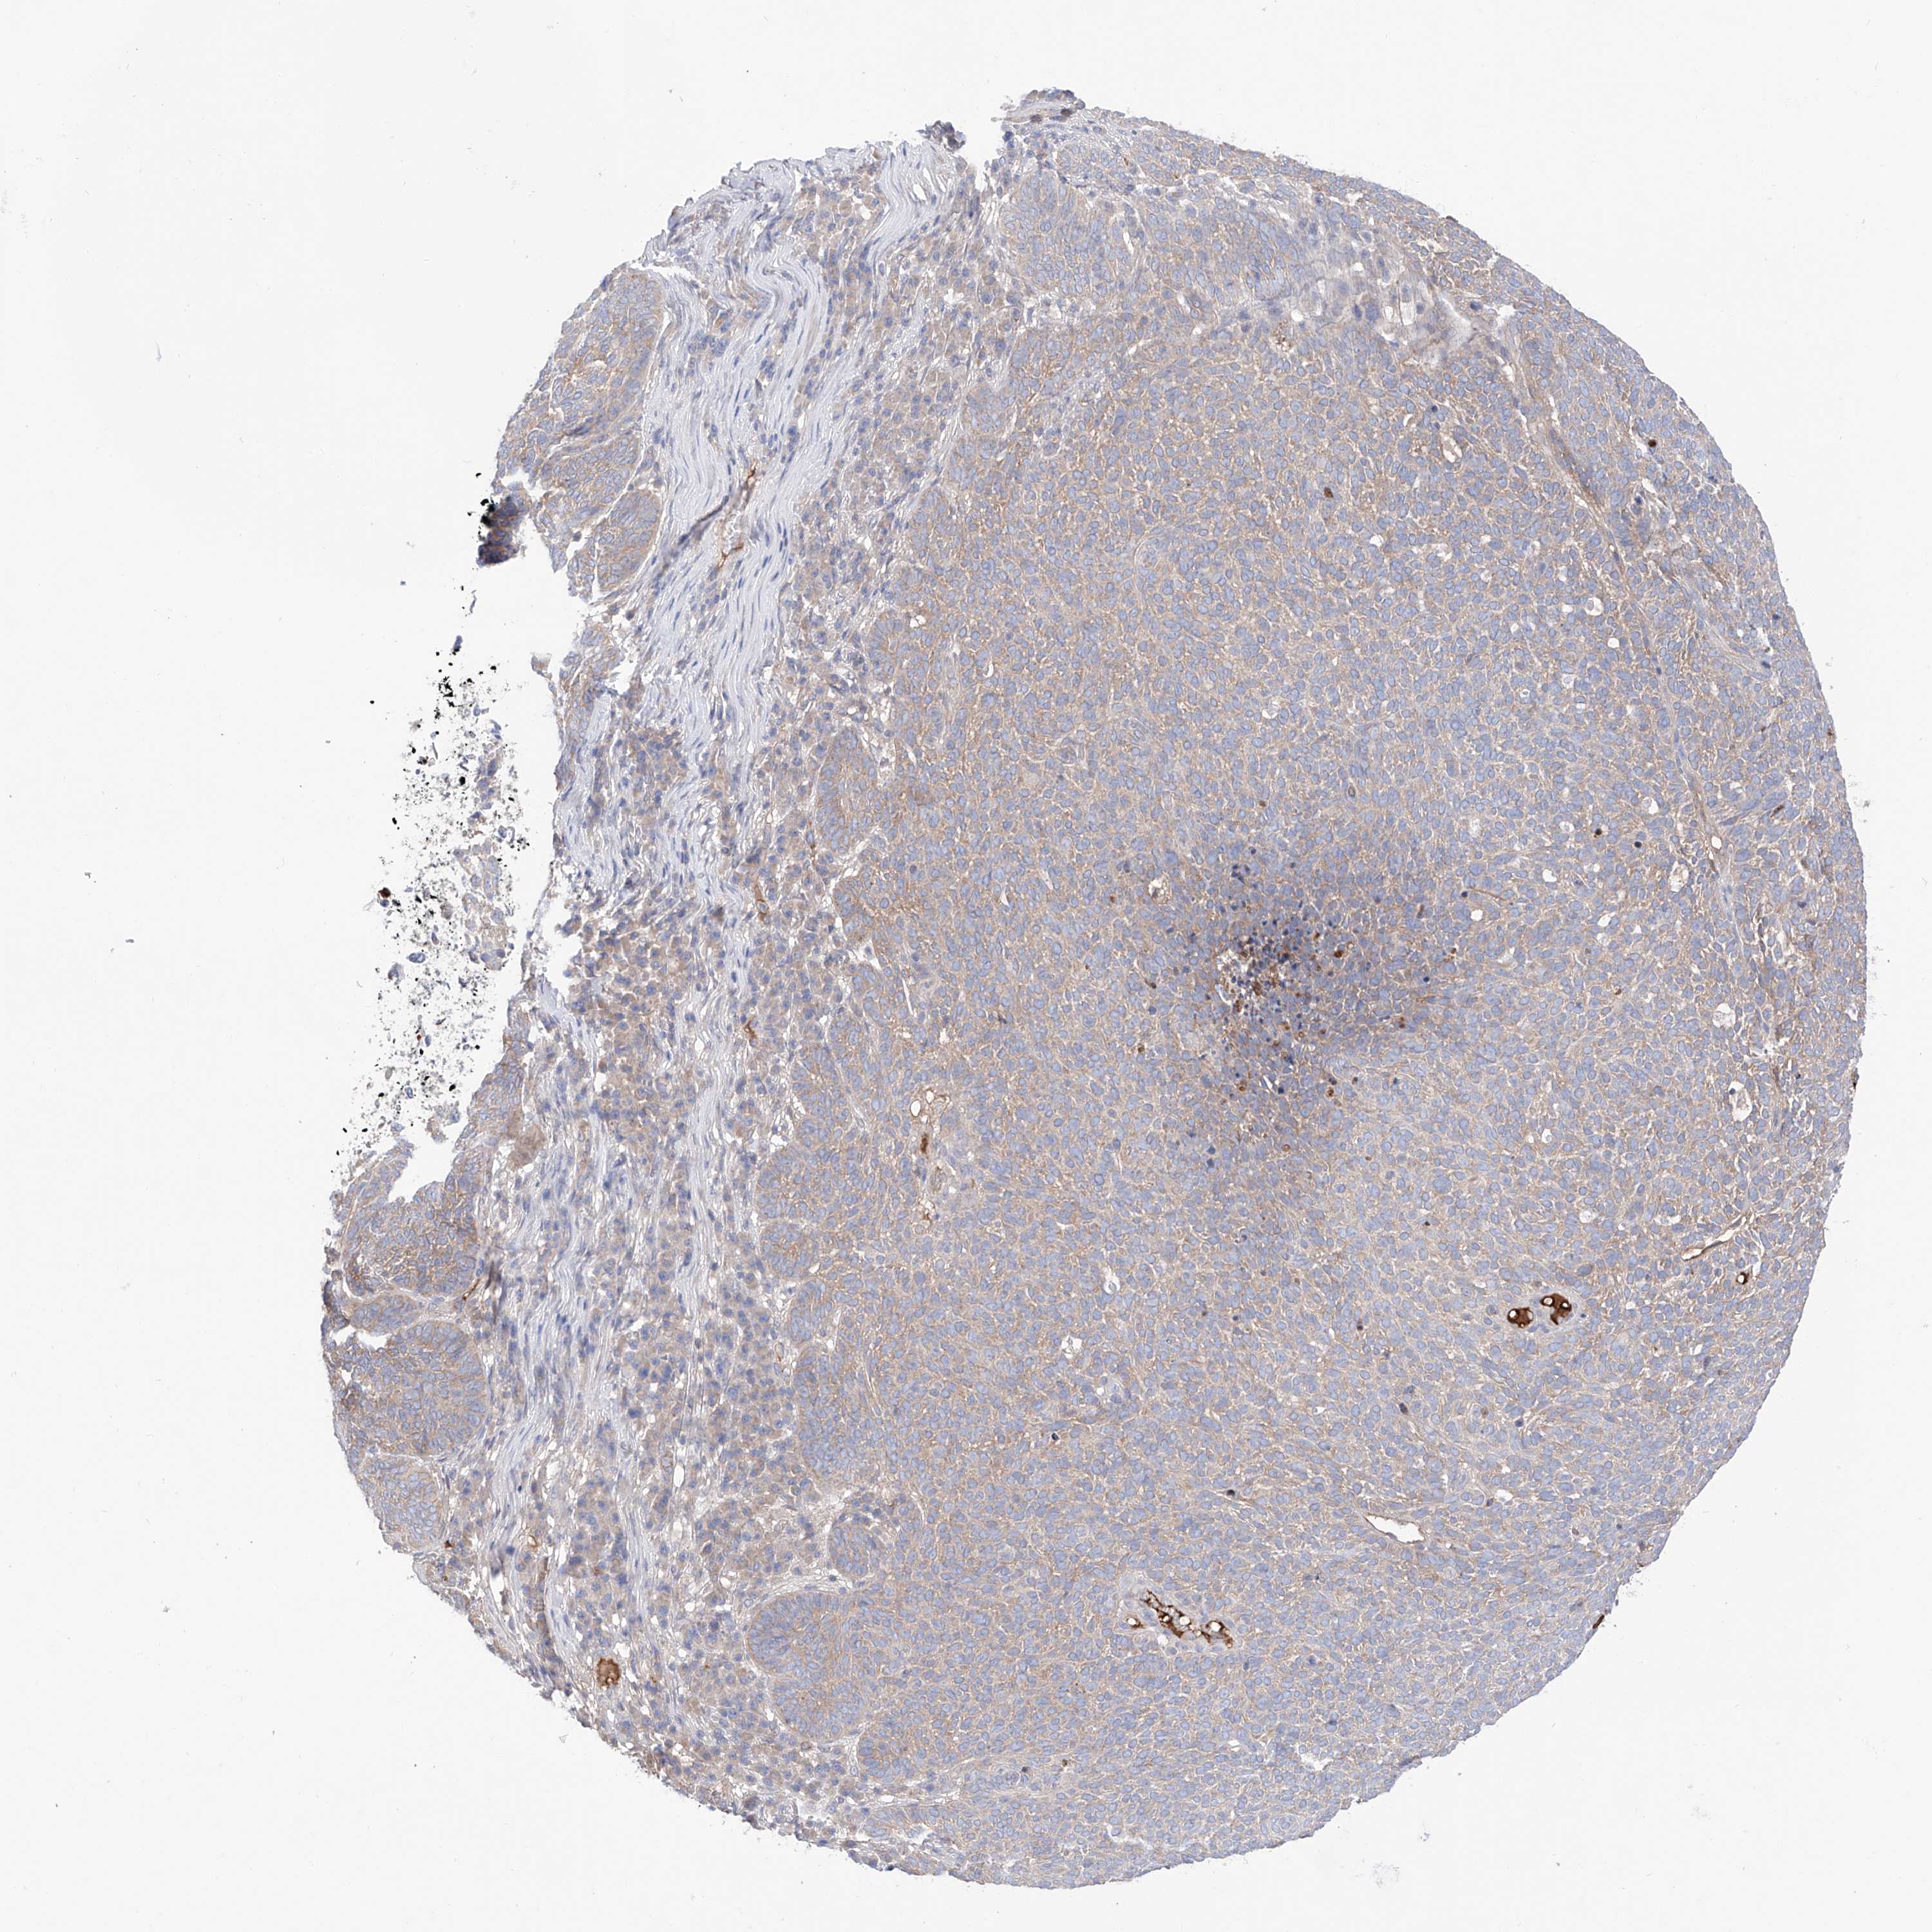

SKIN CANCER - Protein expressioni

A mouse-over function shows sample information and annotation data. Click on an image to view it in a full screen mode. Samples can be filtered based on level of antibody staining by selecting one or several of the following categories: high, medium, low and not detected. The assay and annotation is described here.

Antibody stainingi

Antibody staining in the annotated cell types in the current human tissue is reported as not detected, low, medium, or high, based on conventional immunohistochemistry profiling in selected tissues. This score is based on the combination of the staining intensity and fraction of stained cells.

Each image is clickable and will lead to virtual microscopy that enables deeper exploration of all samples and also displays staining intensity scores, fraction scores and subcellular localization as well as patient and tissue information for each sample.

Antibody HPA030646

Staining

High

Medium

Low

Not detected

Intensity

Strong

Moderate

Weak

Negative

Quantity

>75%

75%-25%

<25%

None

Location

Nuclear

Cytoplasmic/membranous

Cytoplasmic/membranous,nuclear

Basal cell carcinoma